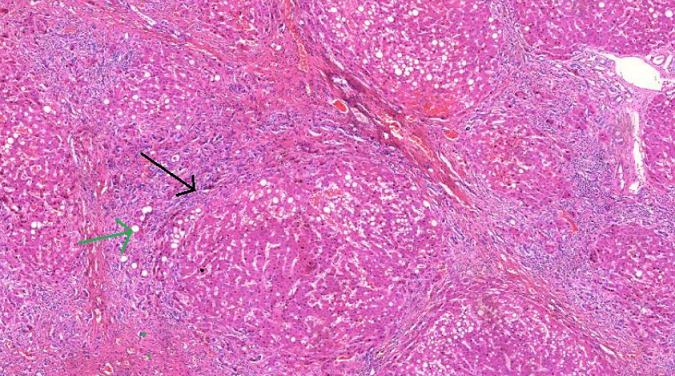

1. Hepatite crônica viral (A534)

1. Processo inflamatório

1. Predomínio de mononucleares no espaço porta ou septos

2. Necrose acometendo espaços periportais

1. Fibrose não difusa

1. Processo irregular

1. Diferencial de cirrose

2. Arquitetura parcialmente preservada

1. Sem nódulos